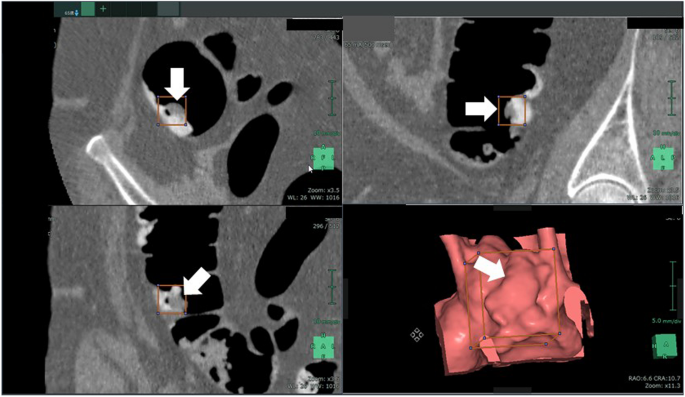

Fig. 2 shows an example of annotation indicating the extent of a colorectal tumor and its coordinates in a CT image used for the development of an AI algorithm. Data regarding the lesion location and size (i.e., circumscribed rectangle) were specified based on the colonoscopy findings and the correct number of lesions included in the CT colonography images used for training and validation. The annotation process and training were carried out by radiologists with experience in reading CT colonography; however no strict rules were imposed. The training and internal validation set were completely randomized during division. Lesions smaller than 6 mm were not assessed in this study.

Annotations for colorectal lesions. Annotation of the bounding rectangle surrounding the colorectal lesions known a priori to be correct on the CT image. CT: computed tomography.

An example of a case in which a lesion within the residue could be detected with low-dose pretreatment and poor tagging is shown in Fig. 5. This lesion was thought to be difficult to detect using CAD that was designed with conventional lesion morphologies that should be detected by a human. The AI algorithm used during this study was able to correctly detect lesions buried in such residue in some cases.

Example case of detecting a lesion embedded in tagging residue. Arrow indicates the lesion of interest.